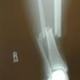

Tib fib fracture

It was Rylands Birthday soo he had people out to his house. It was Alexa, Savanna, Sydney, Brandon, Matt, Clay, Ryland, and Me. well Alexa and Savanna decided they wanted to go put jeans on for the bonfire and we had the brilliant idea to pile on the cub cadet and drive 1 mile over to alexa's house. We were about half way there when we had to turn and we flipped. I hit my face on the roll cage and broke my jaw in two places and was knocked out. then it landed on me causing a tib fib fracture!

i refractured my leg...